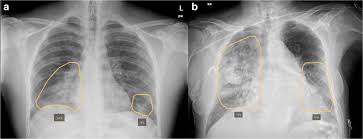

Lymphatic Filariasis, commonly known as elephantiasis, is caused by parasitic worms transmitted through infected mosquitoes. The disease damages the lymphatic system and can lead to severe swelling of body parts, long-term disability, and social stigma. Despite being preventable and treatable, LF has remained a significant public health challenge in several states.